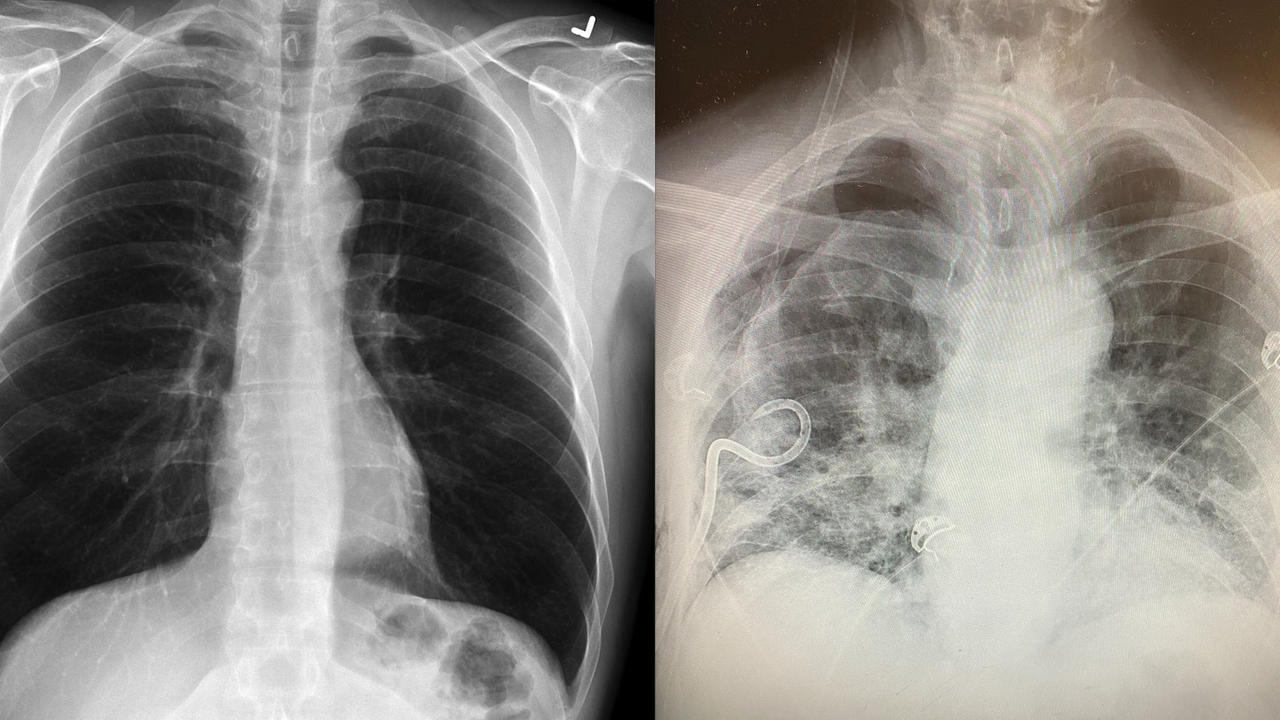

Doctor Most 'probably won't' have longterm lung scarring after COVID Can Lung Scarring Be Seen On Xray the lung scarring and thickening that occurs in pulmonary fibrosis cannot be repaired. the scarring that happens in pulmonary fibrosis can be caused by many things. lab tests can also help providers track disease progression (how it affects your body over time) after. Often, doctors and other healthcare professionals cannot. pulmonary fibrosis is the preferred general. Can Lung Scarring Be Seen On Xray.

Texas surgeon noticing some postCOVID19 lungs have more scar tissue Can Lung Scarring Be Seen On Xray the scarring that happens in pulmonary fibrosis can be caused by many things. lung scarring, known medically as pulmonary fibrosis, can make it difficult to breathe in enough oxygen. lab tests can also help providers track disease progression (how it affects your body over time) after. Often, doctors and other healthcare professionals cannot. the lung scarring. Can Lung Scarring Be Seen On Xray.